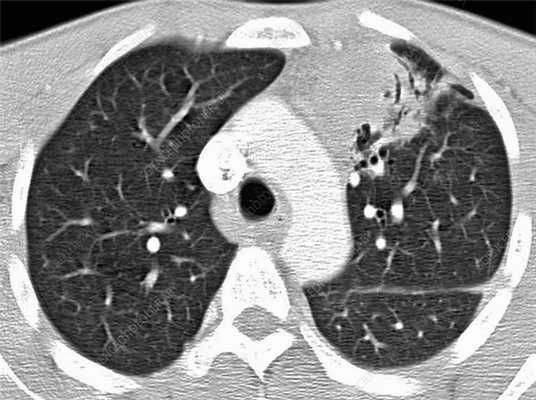

Лимфома легких на КТ

Признаки лимфомы легких особенно выражены на четвертой стадии заболевания, когда болезнь поражает дыхательный орган. На КТ при этом будут видны увеличенные лимфоузлы, формирующие цепочки, конгломераты. При этом у пациента может также наблюдаться отек легких. Однако высокая разрешающая способность КТ позволяет выявить лимфому на ранней, первой стадии.

На КТ лимфомы, как и любые уплотнения, визуализируются сравнительно более светлым цветом. В норме воздушная легочная паренхима практически однородного темного цвета. Иногда таких уплотнений несколько и они диссеминированны. Контуры лимфомы четкие и ровные. Вокруг патологических очагов обнаруживаются участки «матового стекла».

Лимфомы медиастинальной локализации не всегда диагностируются при рентгенологическом обследовании. Компьютерная томография, более детально, чем обзорная рентгенография позволяет рассмотреть конгломерат опухоли, увеличение лимфоузлов средостения, вовлечение паратрахеальных, трахеобронхиальных, прикорневых лимфатических узлов. Диагностическая значимость магнитно-резонансной томографии в верификации лимфом средостения признается не всеми авторами.